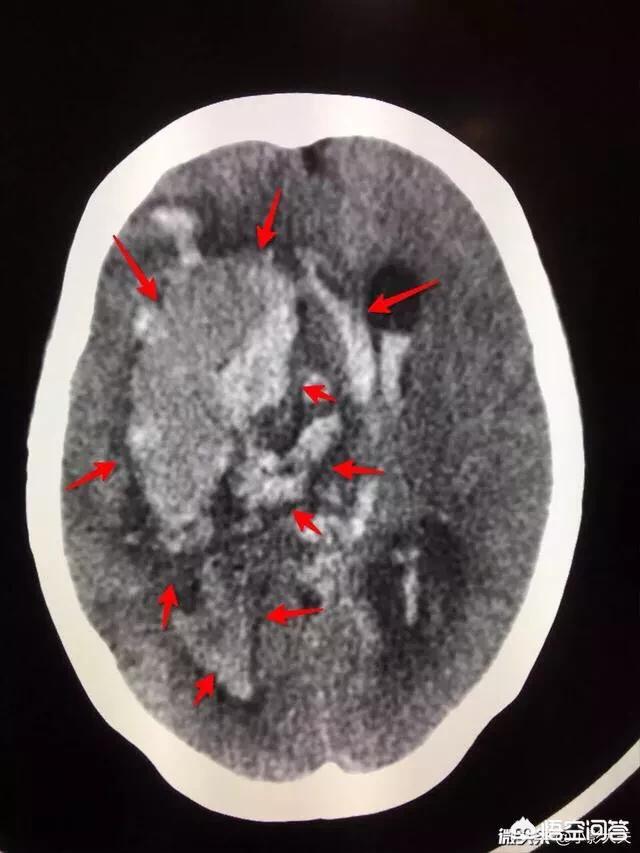

Encéphalopathie hypertensive, hémorragie cérébrale. En clinique, lorsque des personnes âgées se présentent avec des vertiges et des céphalées et qu'un scanner révèle une hémorragie cérébrale dans la région des ganglions de la base, 80 % d'entre elles ont des antécédents d'hypertension, et la plupart sont des patients qui savent qu'ils ont une tension artérielle élevée mais qui ne la contrôlent pas, ou qui prennent le médicament pendant un jour et l'arrêtent pendant quelques jours. L'hémorragie cérébrale hypertensive la plus récente jamais observée concernait un patient de 30 ans, qui savait qu'il souffrait d'hypertension, mais qui pensait qu'il était jeune et que tout irait bien, et qui n'a donc pas cherché à se faire soigner.

Il s'agit d'une grand-mère de 75 ans, agricultrice. Elle a été retrouvée inconsciente dans les toilettes à 8h15. Elle a été admise en urgence et sa tension artérielle a été mesurée à 233/122 mmHg (normale 140/90). Le scanner a révélé une hémorragie crânienne avec au moins 200 ml de sang, une hémorragie du tronc cérébral, une hémorragie ventriculaire et une hernie cérébrale. Son cerveau était plein de sang. L'état de santé était très grave et, après avoir fait savoir à la famille que le pronostic était mauvais, celle-ci a décidé d'abandonner le traitement.